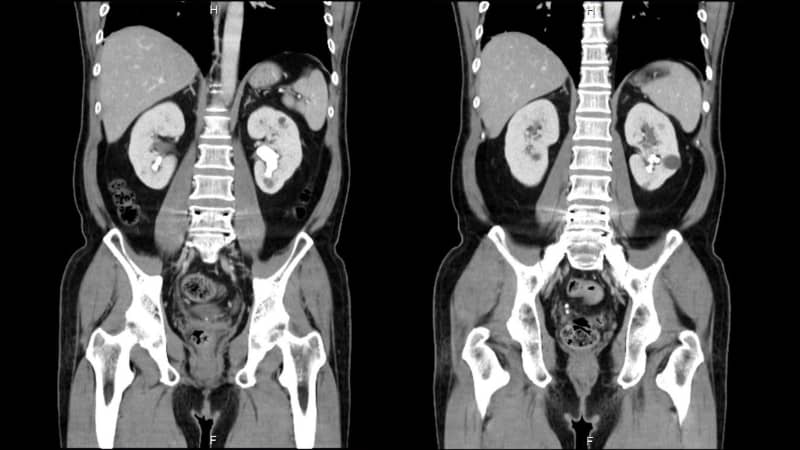

56 歲的楊先生正值壯年,身為家中經濟支柱,卻長期受雙側腰部酸痛及反覆血尿所苦。經衛福部雙和醫院泌尿科 – 董劭偉醫師檢查發現:其病情較為複雜屬於複雜型腎結石,雙側腎臟皆有結石,尤其左側腎臟為最長徑達 3 公分的「 部分鹿角結石 」並延伸至下腎盞,右側同樣有下腎盞結石。

董劭偉醫師解釋,像楊先生左側最長達 3 公分的「 部分鹿角結石 」被視為手術的大魔王,因其結石分支延伸至不同腎盞,尤其下腎盞位於腎臟最底部,角度非常刁鑽。